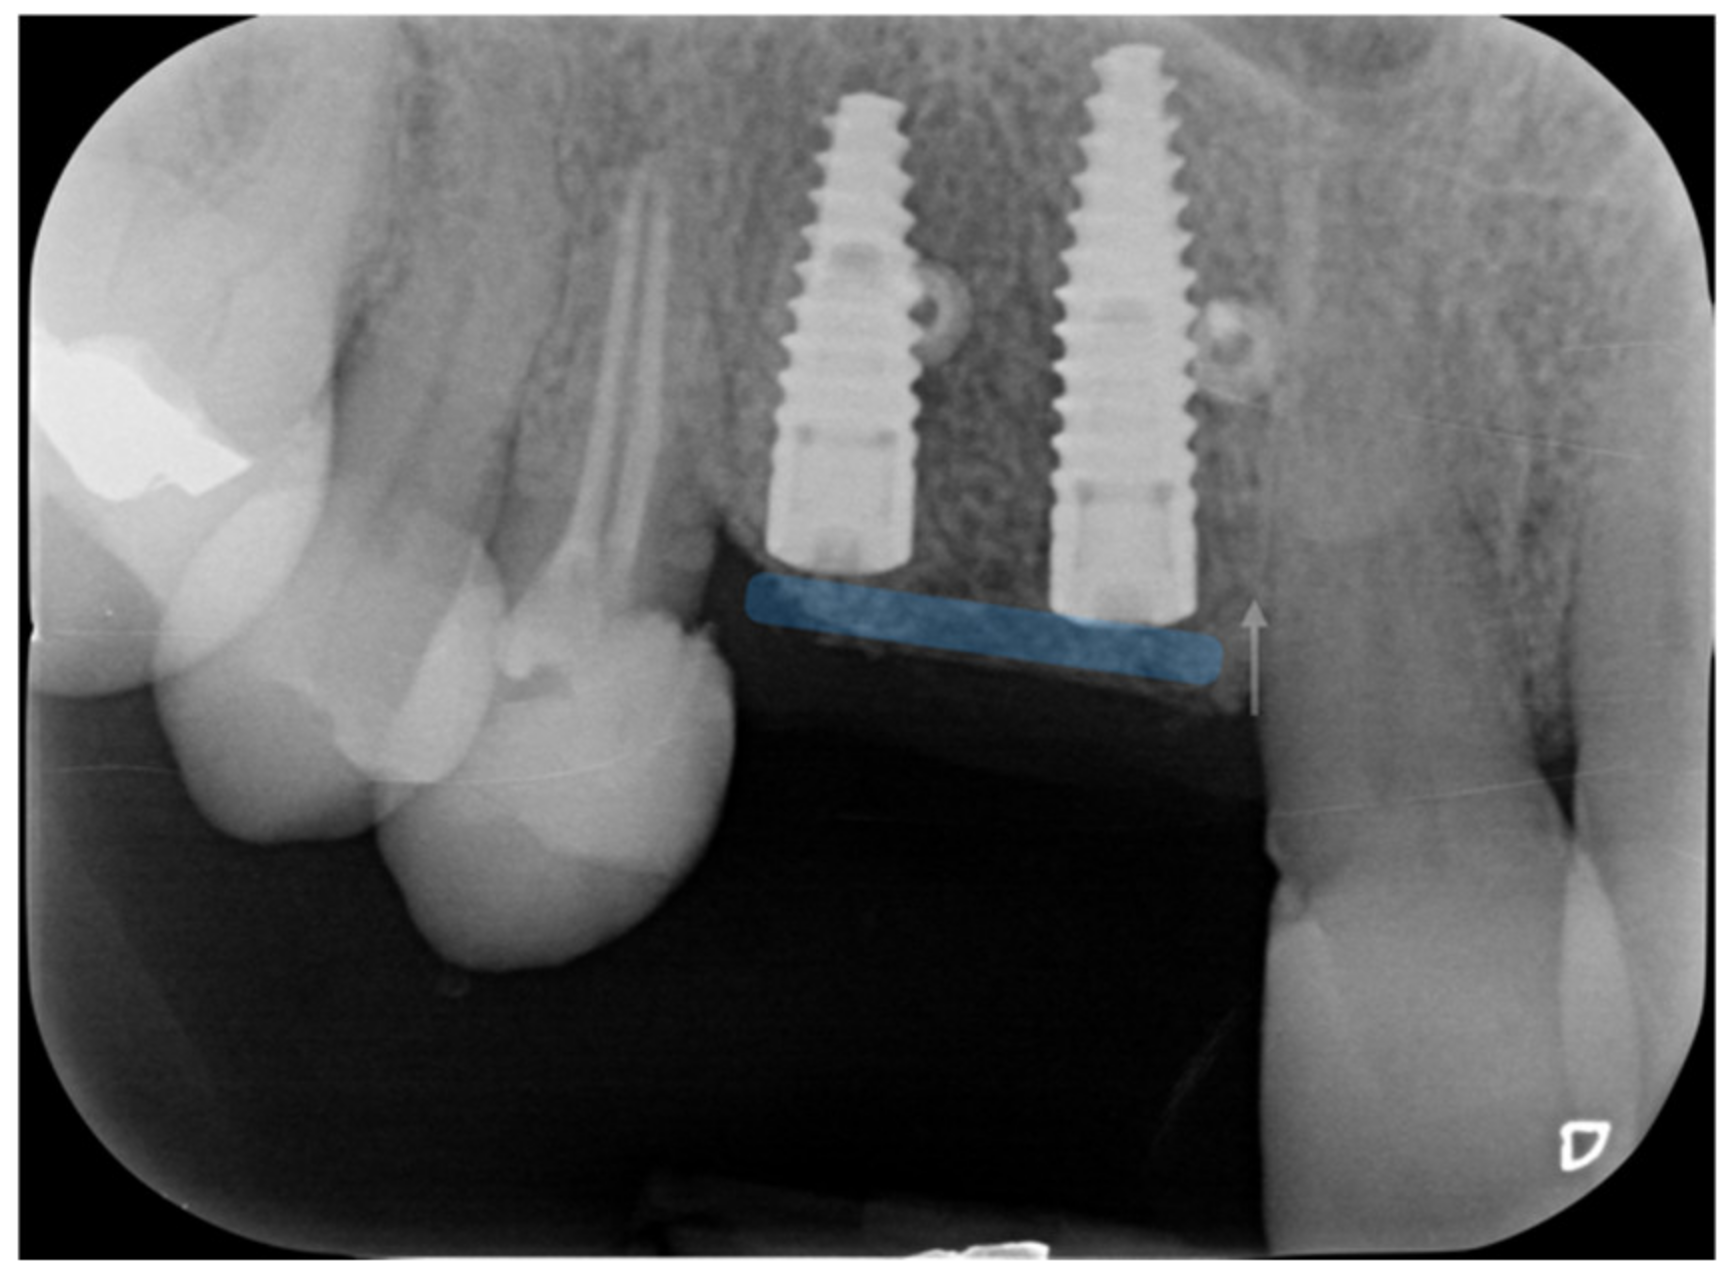

The radiographs at baseline and after completion of the prosthetic restoration also show the GTR effect of GBR in this case on the natural teeth, aside from the expected effect on bone and implants. Both bony peaks to the distal of 11 and mesial of 14 are coronal to the head of the fixture and support interdental papilla (Figure 20 and Figure 21). It is possible to appreciate in the radiographs the stability and good mineralization of the grafted area.

Figure 20.

The supra-crestal component of the bone lamina (blue) and the GTR effect near tooth 11 (white arrow).